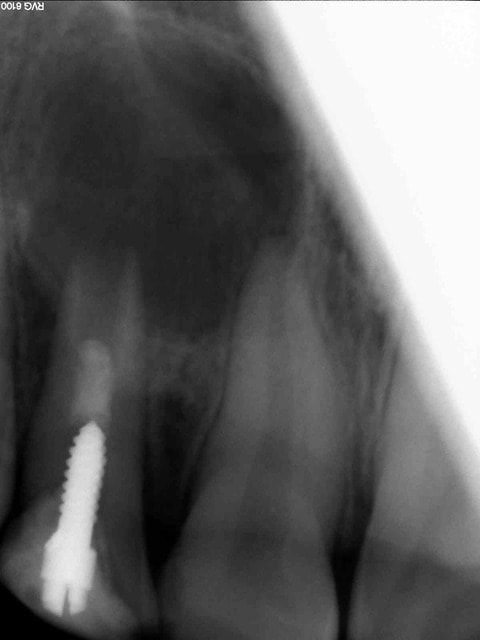

Autre cas avec petite modification dans le protocole pour éviter les mésaventures du cas précédent :

Adulte (dens in dente qui a entrainé la nécrose de la dent)

J'ai placé des éponges hémostatiques au delà de l'apex ce qui permet de créer un matelas plus dense à la limite de la racine et ainsi de condenser plus sereinement le MTA.

--